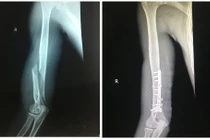

Khi vật tay, lực xoay đột ngột tác động lên xương cánh tay có thể vượt ngưỡng chịu đựng, gây gãy xoắn xương cánh tay, thậm chí di lệch.